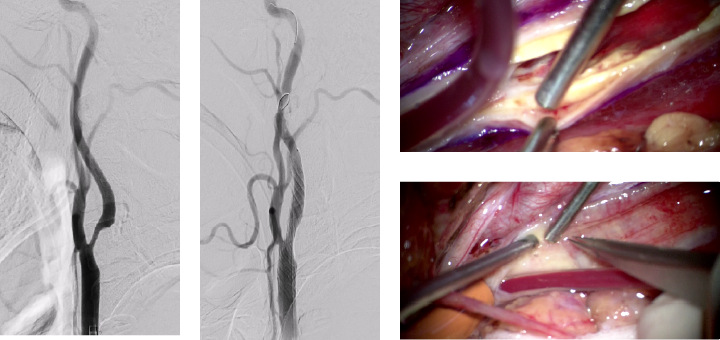

脳に酸素と栄養を送る血管が詰まる病気(脳梗塞)は重度の後遺症を生じる可能性のある大変恐ろしい病気で、当科では予防と万が一の際の治療の両面に対して全道トップレベルの治療を提供しています。予防には内服治療・手術治療・カテーテル治療など複数の治療選択肢がありますが、当科では日本をリードする技術・知識を有する専門医・指導医がチームを形成し、患者さん一人一人に合った最適な治療法を提示しております。また、万が一の際にも最新の医療技術・機器を駆使し高度な医療を要する三次救急施設としての役割を担い治療に当たっています。大学病院ならではのハイレベルな医療連携を活用する事で、透析中の方や膠原病・悪性腫瘍を患っている方など全身管理が非常に難しい患者さんに対して対応できるのも当科の強みです。